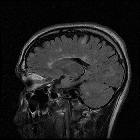

The clothes

maketh the sign. Sagittal fluid attenuated inversion recovery MRI sequence depicting several adjacent high signal pericallosal lesions resembling adjacent jewels in a Venus flytrap necklace, a style popular in the 1920s. The high signal lesions correlate with demyelinating plaques which typically arise in a perivenous location, the arrangement of lesions, at right angles to the corpus callosum, represents the distribution of callososeptal medullary veins, the appearance has also been described as “Dawson fingers”